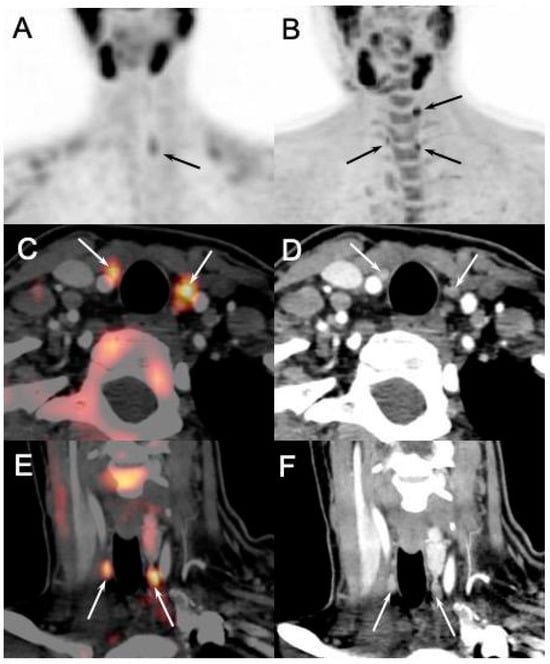

Figure 4. Enlarged left superior parathyroid in 53-year-old woman with primary hyperparathyroidism. Yellow arrow indicates 9 mm soft tissue nodule located posteriorly to third medium of left thyroid lobe, hypodense to thyroid parenchyma on non-contrast-enhanced phase (A), hyper enhancing on arterial phase (B) with subsequent wash-out on delayed phase (C). Reformatted sagittal (D), coronal (E), and axial (F) maximum intensity projection images obtained by arterial phase scan demonstrate upper enlarged polar vessel.

Figure 7. Discordant results of [99mTc]sestamibi parathyroid scintigraphy ((A): anterior MIP) and [18F]FCH PET/4D-CT ((B): anterior MIP; (C,E): axial and coronal fusion images; (D,F): axial and coronal 4D-CT) performed in 28-y-old MEN1 patient with recurrent primary hyperparathyroidism (PTH: 133 ng/L; calcemia: 2.70 mmol/L). [18F]FCH PET/CT confirmed scintigraphy findings (pathological left inferior gland) and detected two more hyperfunctioning parathyroids tumors (arrows, inferior right and superior left) afterwards confirmed by pathology.